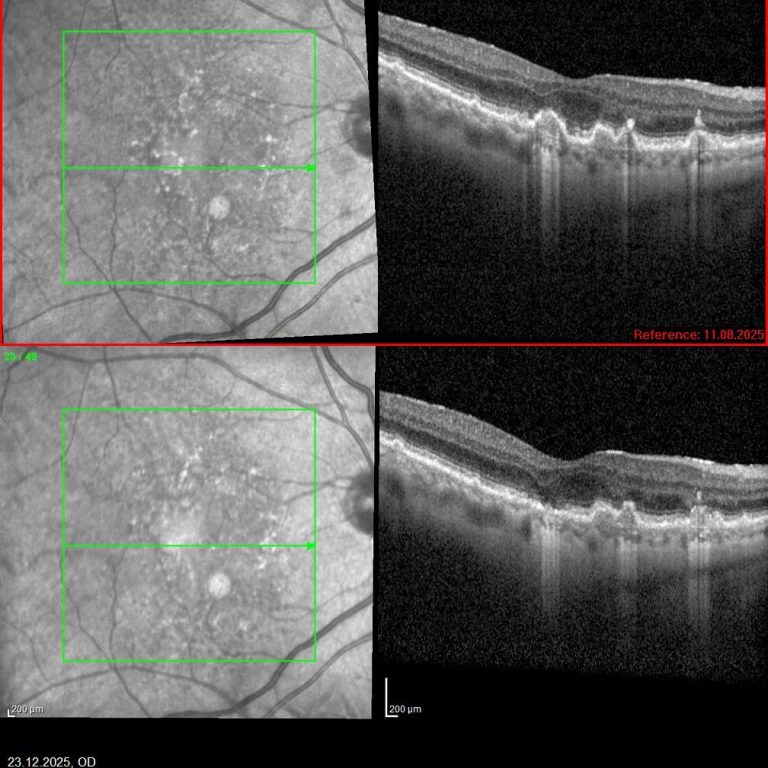

Auf der linken und rechten Seite sehen wir den jeweils gleichen Schnitt durch die Netzhaut an unterschiedlichen Zeitpunkten (links nach etwa 4, rechts nach etwa 8 Monaten) unterschiedlicher Patienten nach 9 Sitzungen Photobiomodulation (PBM). Der therapeutische Effekt mit Reduktion der Ablagerungen (Drusen) unterhalb der Netzhaut und retinalem Pigmentepithels zeigt sich rechts wie links.